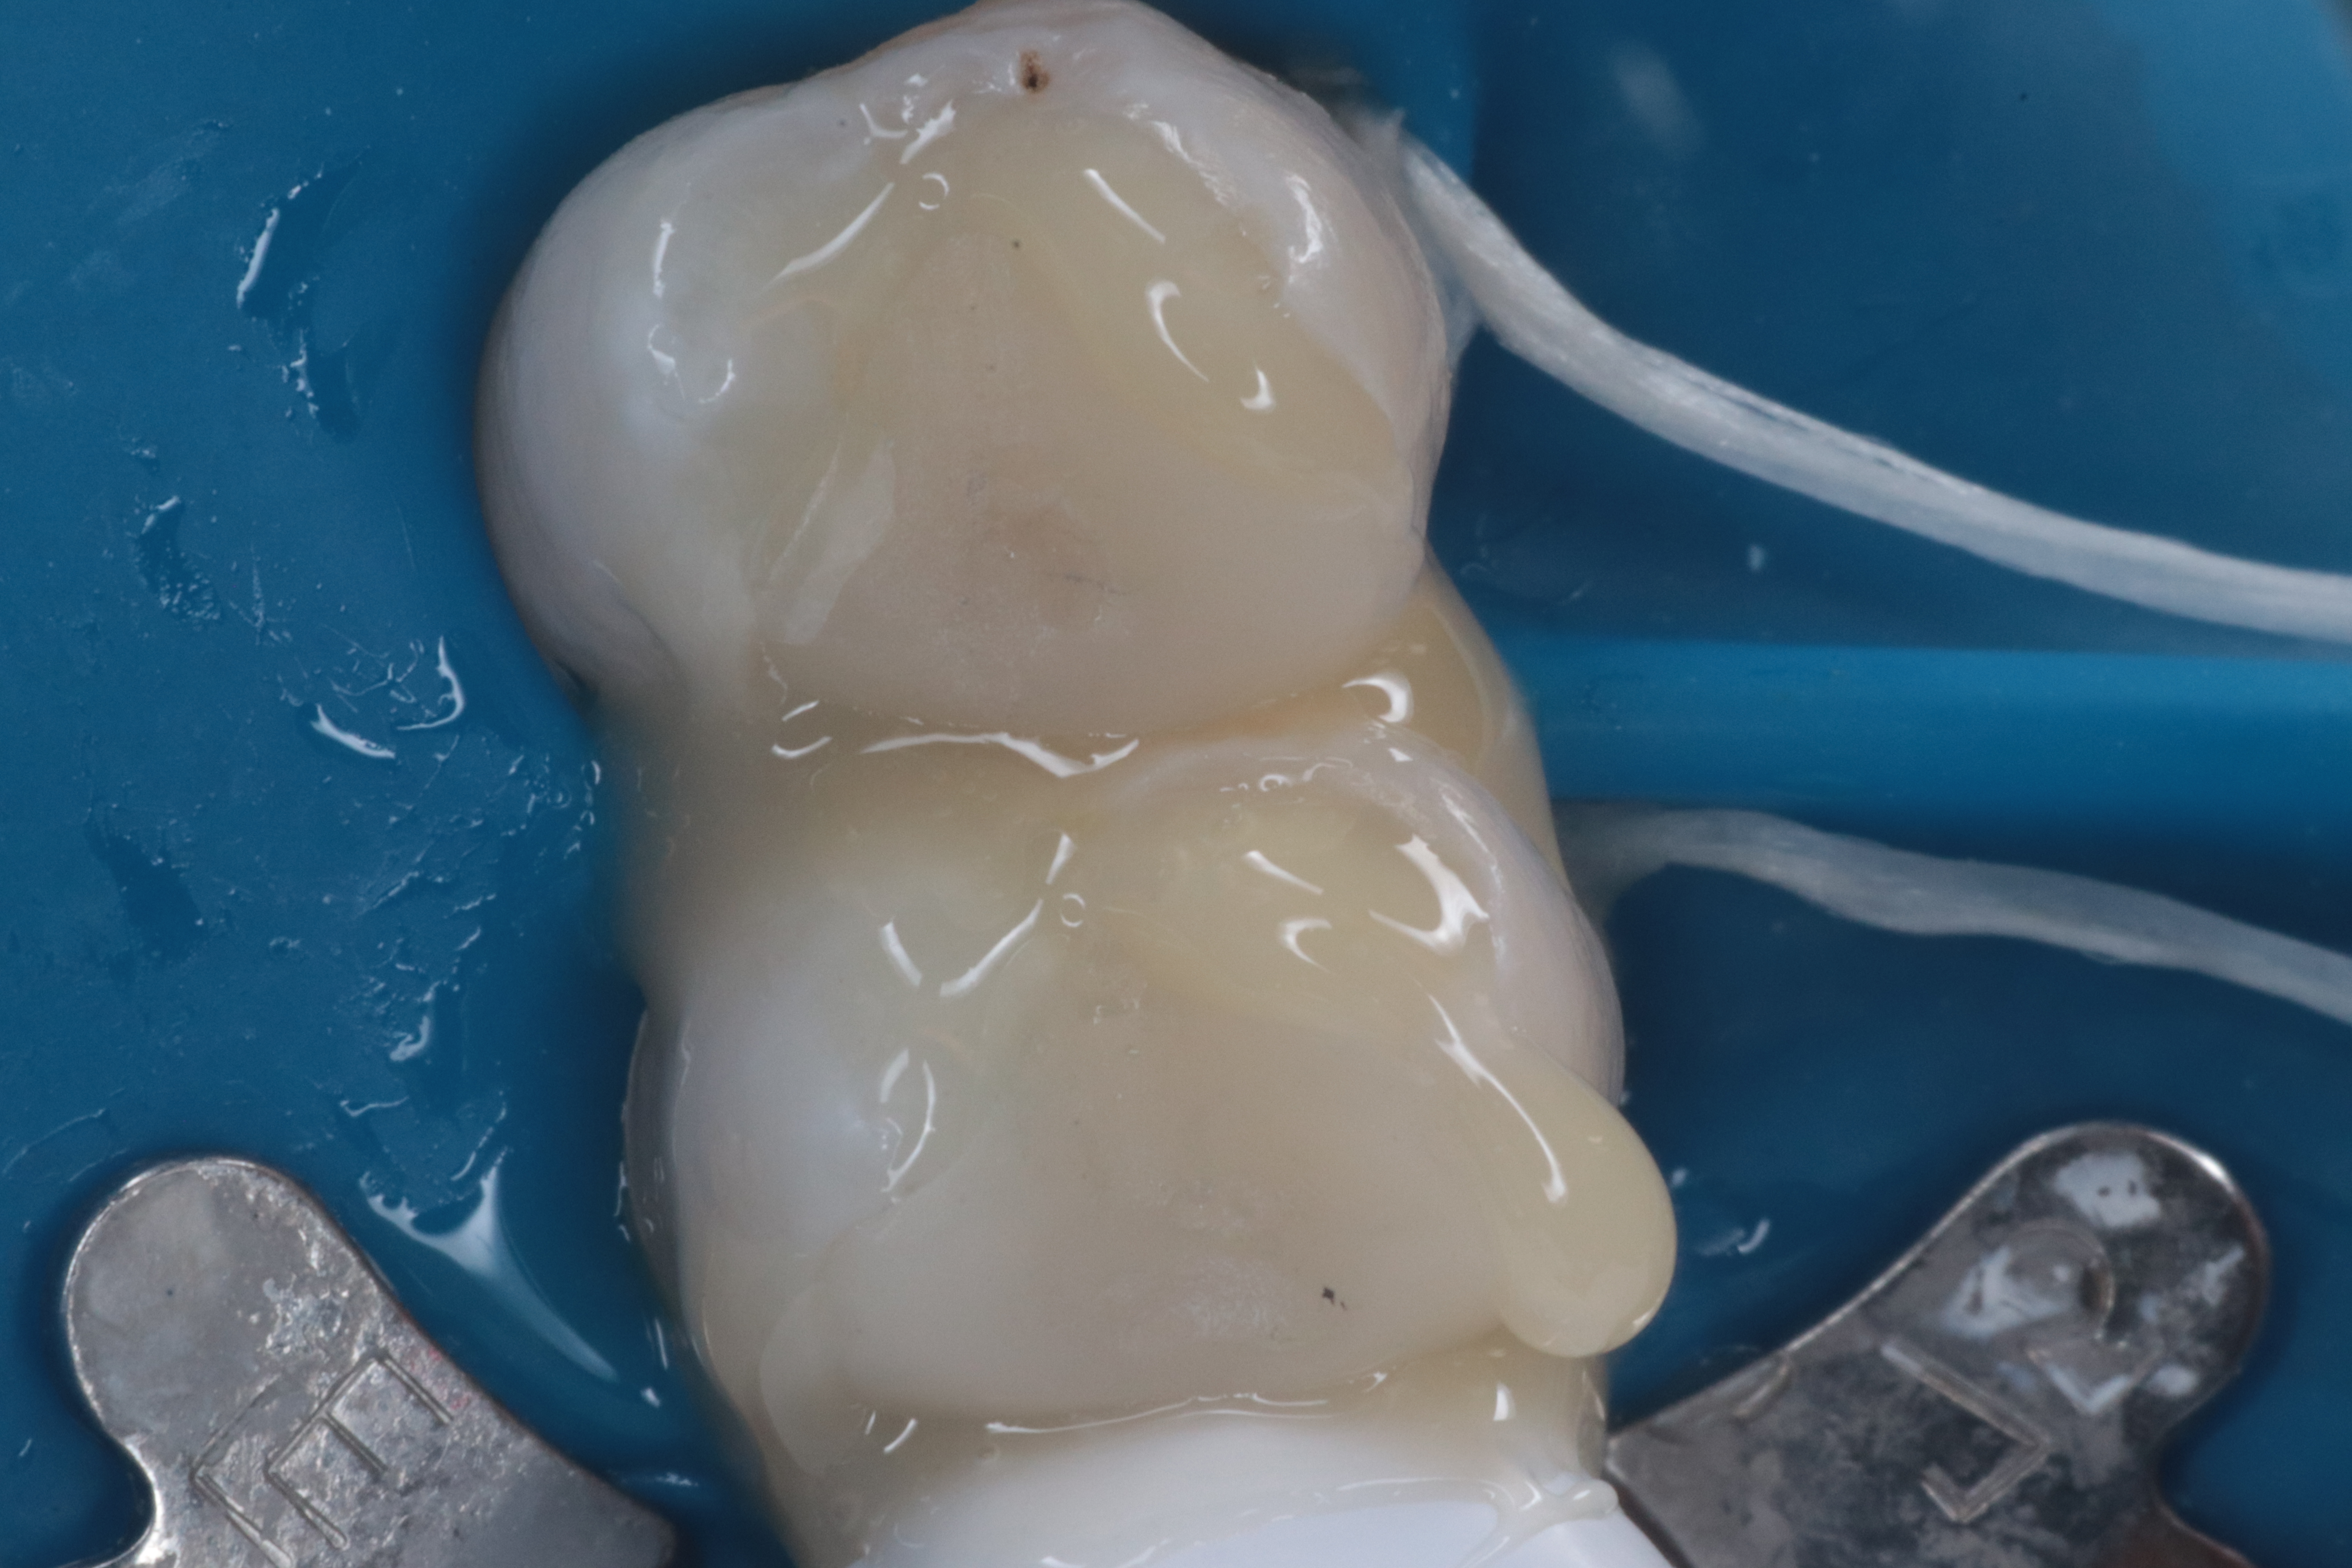

画像で見える真ん中の歯の詰め物が外れたということで来院されました。

その歯と、その歯の一つ上に見える歯を修復するということで、今回はセレックシステムを使用して修復しました。

セット前に試し入れをします。

セレックシステムだと、これぐらいの精度で修復物を製作することになります。臨床上問題ありませんが、個人的にはシリコン印象で製作したe-mas pressの適合のほうが勝ると考えています(過去記事参照)。